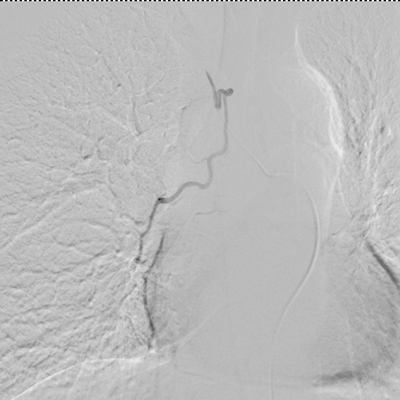

患者王某、男、55岁,因“反复间断咯血3月余”入住我院,曾因间断咯血,多次行止血药物等治疗,但症状仍有反复。此次咯血量大,病情危重,药物治疗效果差,经院内多学科讨论,在湖北民族大学附属民大医院副主任医师万金城、主治医师姚蓬指导下,制定血管介入治疗方案,并顺利完成了支气管动脉造影术+支气管动脉栓塞术,术后患者咯血症状明显好转。

术前 术后